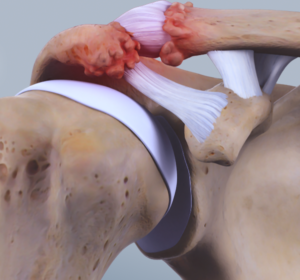

Bij verouderen kan een slijtage ontstaan van het gewricht. Het kraakbeen slijt af, de botuiteinden gaan tegen elkaar wrijven en geven uiteindelijk pijnklachten. Vaak gaat dit gepaard met het ontstaan van papegaaienbekken (osteofyten) aan de onderzijde van het gewricht. Deze papegaaienbekken gaan duwen op de onderliggende schouderpees en op die manier een soort inklemming veroorzaken.

Anatomie van het acromio-claviculair gewricht AC-gewricht met arthrose - kraakbeenslijtage

OPERATIEVE BEHANDELING = AC resectie, mumford operatie

Via kijkoperatie wordt een volledige inspectie gedaan van het schouder gewricht om andere oorzaken van schouderpijn uit te sluiten. Steeds wordt de subacromiale ruimte groter gemaakt (=subacromiale decompressie) en worden alle papegaaienbekken verwijderd. Nadien wordt een stukje van het aangetaste, kapotte kraakbeen uiteinde van het sleutelbeen verwijderd. De ruimte die ontstaat aan het uiteinde van het sleutelbeen vult zich spontaan op met littekenweefsel.

Arthroscopische AC-gewricht resectie Distale clavicula excisie bij AC-artrose